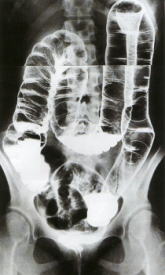

【大腸X線検査】

肛門からバリウムを注入しそれをX線で調べます。

小さな病変や平たんな病変の診断能力は内視鏡には及びませんが、憩室のような大腸の内腔から見ると凹んだ病変の診断や大腸のひだによる死角が少ない点では優れていると思われます。